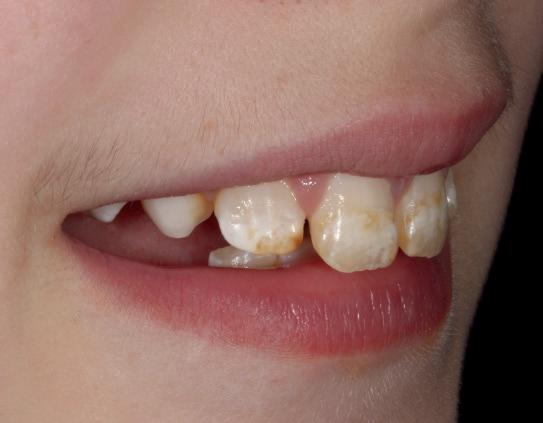

Rise of the Internet dental diagnosis

From the bizarre, and the ridiculous to the positively dangerous, online ‘dentistry’ has been blooming in popularity

As of January 2024, there were 5.35 billion internet users worldwide, which amounted to 66.2% of the global population. Of this total, 5.04 billion, or 62.3% of the world’s population, were social media users. 1

It is hard to get an exact number of those who are regularly performing dentistry on themselves. However, in February, polling by the British Dental Association (BDA) revealed that 82% of dentists are treating gruesome cases of DIY dentistry. 2

The internet and social media are part of our everyday lives. It is easy to understand why some people are turning to the internet for advice. The ongoing dental access crisis that has been building over the last few years, has left many desperate for dental advice wherever they can get it.

Why not get it at the touch of a phone screen?

Like a lot of the information that can be found on the internet, this advice may not be coming from a dental professional. At best, the advice may be useless. At worse, it could actually damage a patient’s teeth and gums.

Reams of misinformation and wrong claims abound on the internet. You can visit sites such as TikTok to investigate all the ways people are putting their smiles in danger.

Influencers are recommending rubbing fruit like strawberries and lemons on their teeth constantly to whiten them. Filing their teeth with a nail file so they look straighter. Using nail glue to fix their loose teeth to the gums.

These examples are certain to send a shudder of horror through any dental professional when their patients admit to attempting them. These types of DIY dentistry can cause permanent damage to patients’ mouths.

More importantly, these practices can cause pain and be costly to correct, putting pressure on the dentist to perform miracles and undo the damage.